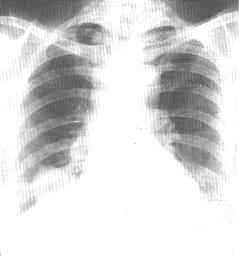

1、X線表現:

(1)中央型:可呈肺氣腫或支擴引起的柱狀密度增高影,呈手套征。腫瘤較大時可表現為一側肺、肺葉或肺段阻塞性肺炎或肺不張。管外型或混合型瘤體在肺門區可形成圓形或橢圓形腫塊。體層攝影可見支氣管內息肉狀或球形軟組織影,邊緣光滑銳利、密度均勻。也可顯示管壁增厚,管腔狹窄,圍繞支氣管的軟組織腫物影。腔內生長可見局部管腔略增寬。

(2)周圍型:可見肺內球形或不規則形腫塊陰影,邊緣光滑銳利,密度中等,沒有鈣化,以2.5~5cm大小多見。無特徵性改變。

支氣管腺瘤 X線表現 | 支氣管腺瘤 CT表現 | 支氣管腺瘤 CT表現 |